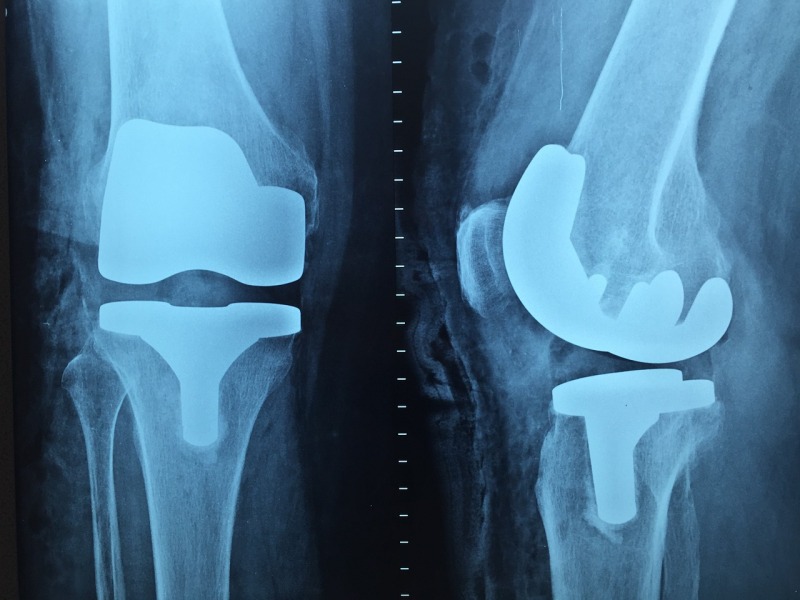

Teleradiologia, stanowiąc jeden z kluczowych elementów telemedycyny, rewolucjonizuje proces diagnostyczny w medycynie, oferując rozwiązania, które znacząco przyspieszają i usprawniają dostęp do specjalistycznych usług radiologicznych. Technologia ta umożliwia przesyłanie cyfrowych obrazów medycznych, takich jak zdjęcia rentgenowskie, obrazy z tomografii komputerowej (CT) czy rezonansu magnetycznego (MRI), między placówkami medycznymi na odległość, co pozwala na szybką interpretację wyników przez specjalistów, nawet jeśli znajdują się oni w innej części kraju, czy nawet świata.

Proces teleradiologiczny rozpoczyna się od przeprowadzenia badania diagnostycznego, które jest następnie cyfrowo przetwarzane. Dane te są wysyłane do centrum teleradiologicznego, takiego jak firma Tele Diagnostyka https://telediag.pl/, która specjalizuje się w świadczeniu usług związanych z teleradiologią. W centrum doświadczeni radiolodzy dokonują analizy przesłanych obrazów. Oferują oni szczegółowy opis wyników, który jest przekazywany lekarzowi prowadzącemu pacjenta. Taka współpraca pozwala na błyskawiczne podjęcie decyzji dotyczących dalszego leczenia, co jest niezwykle ważne w przypadku chorób wymagających szybkiej interwencji.